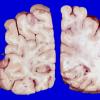

MYELIN (NON-IMMUNE MEDIATED)

Fat Embolism (9)